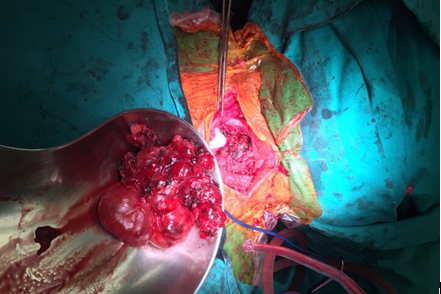

Bệnh nhân có chỉ định phẫu thuật ngày 5/9/2018. Quá trình phẫu thuật rất khó khăn do khối u lớn chui sâu vào trong lồng ngực, rất nhiều mạch máu tăng sinh, bệnh nhân lại có tiền sử phẫu thuật trước đó nên khối u dính chặt vào tổ chức xung quanh rất khó bóc tách. Sau hơn 2 giờ, cuộc phẫu thuật đã thành công lấy ra khối u lớn đường kính 8×10 cm.

HÌnh ảnh trong mổ